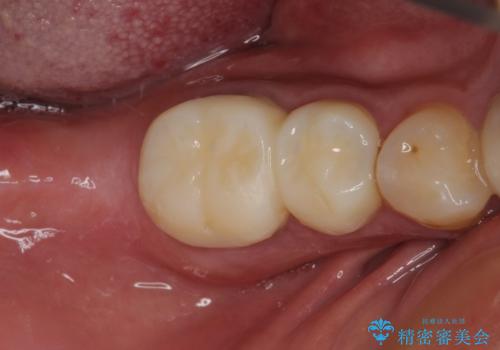

小さい修復物の銀歯が装着されている歯はセラミックインレーにて、その他はオールセラミッククラウンにて補綴治療を進めることとしました。